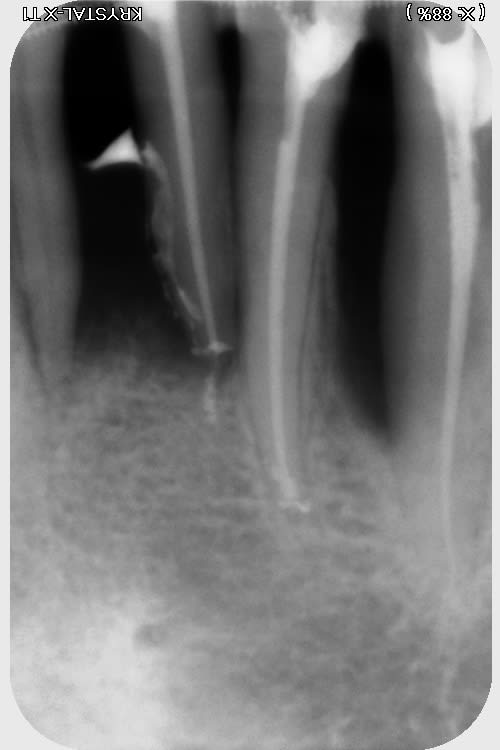

j'ai trouvé ça...rien de parfait malgré l'utilisation de broches manuelle, en alternance avec les rotatives sur certaines racine "légèrement coudées"....

pano et scan plus tard